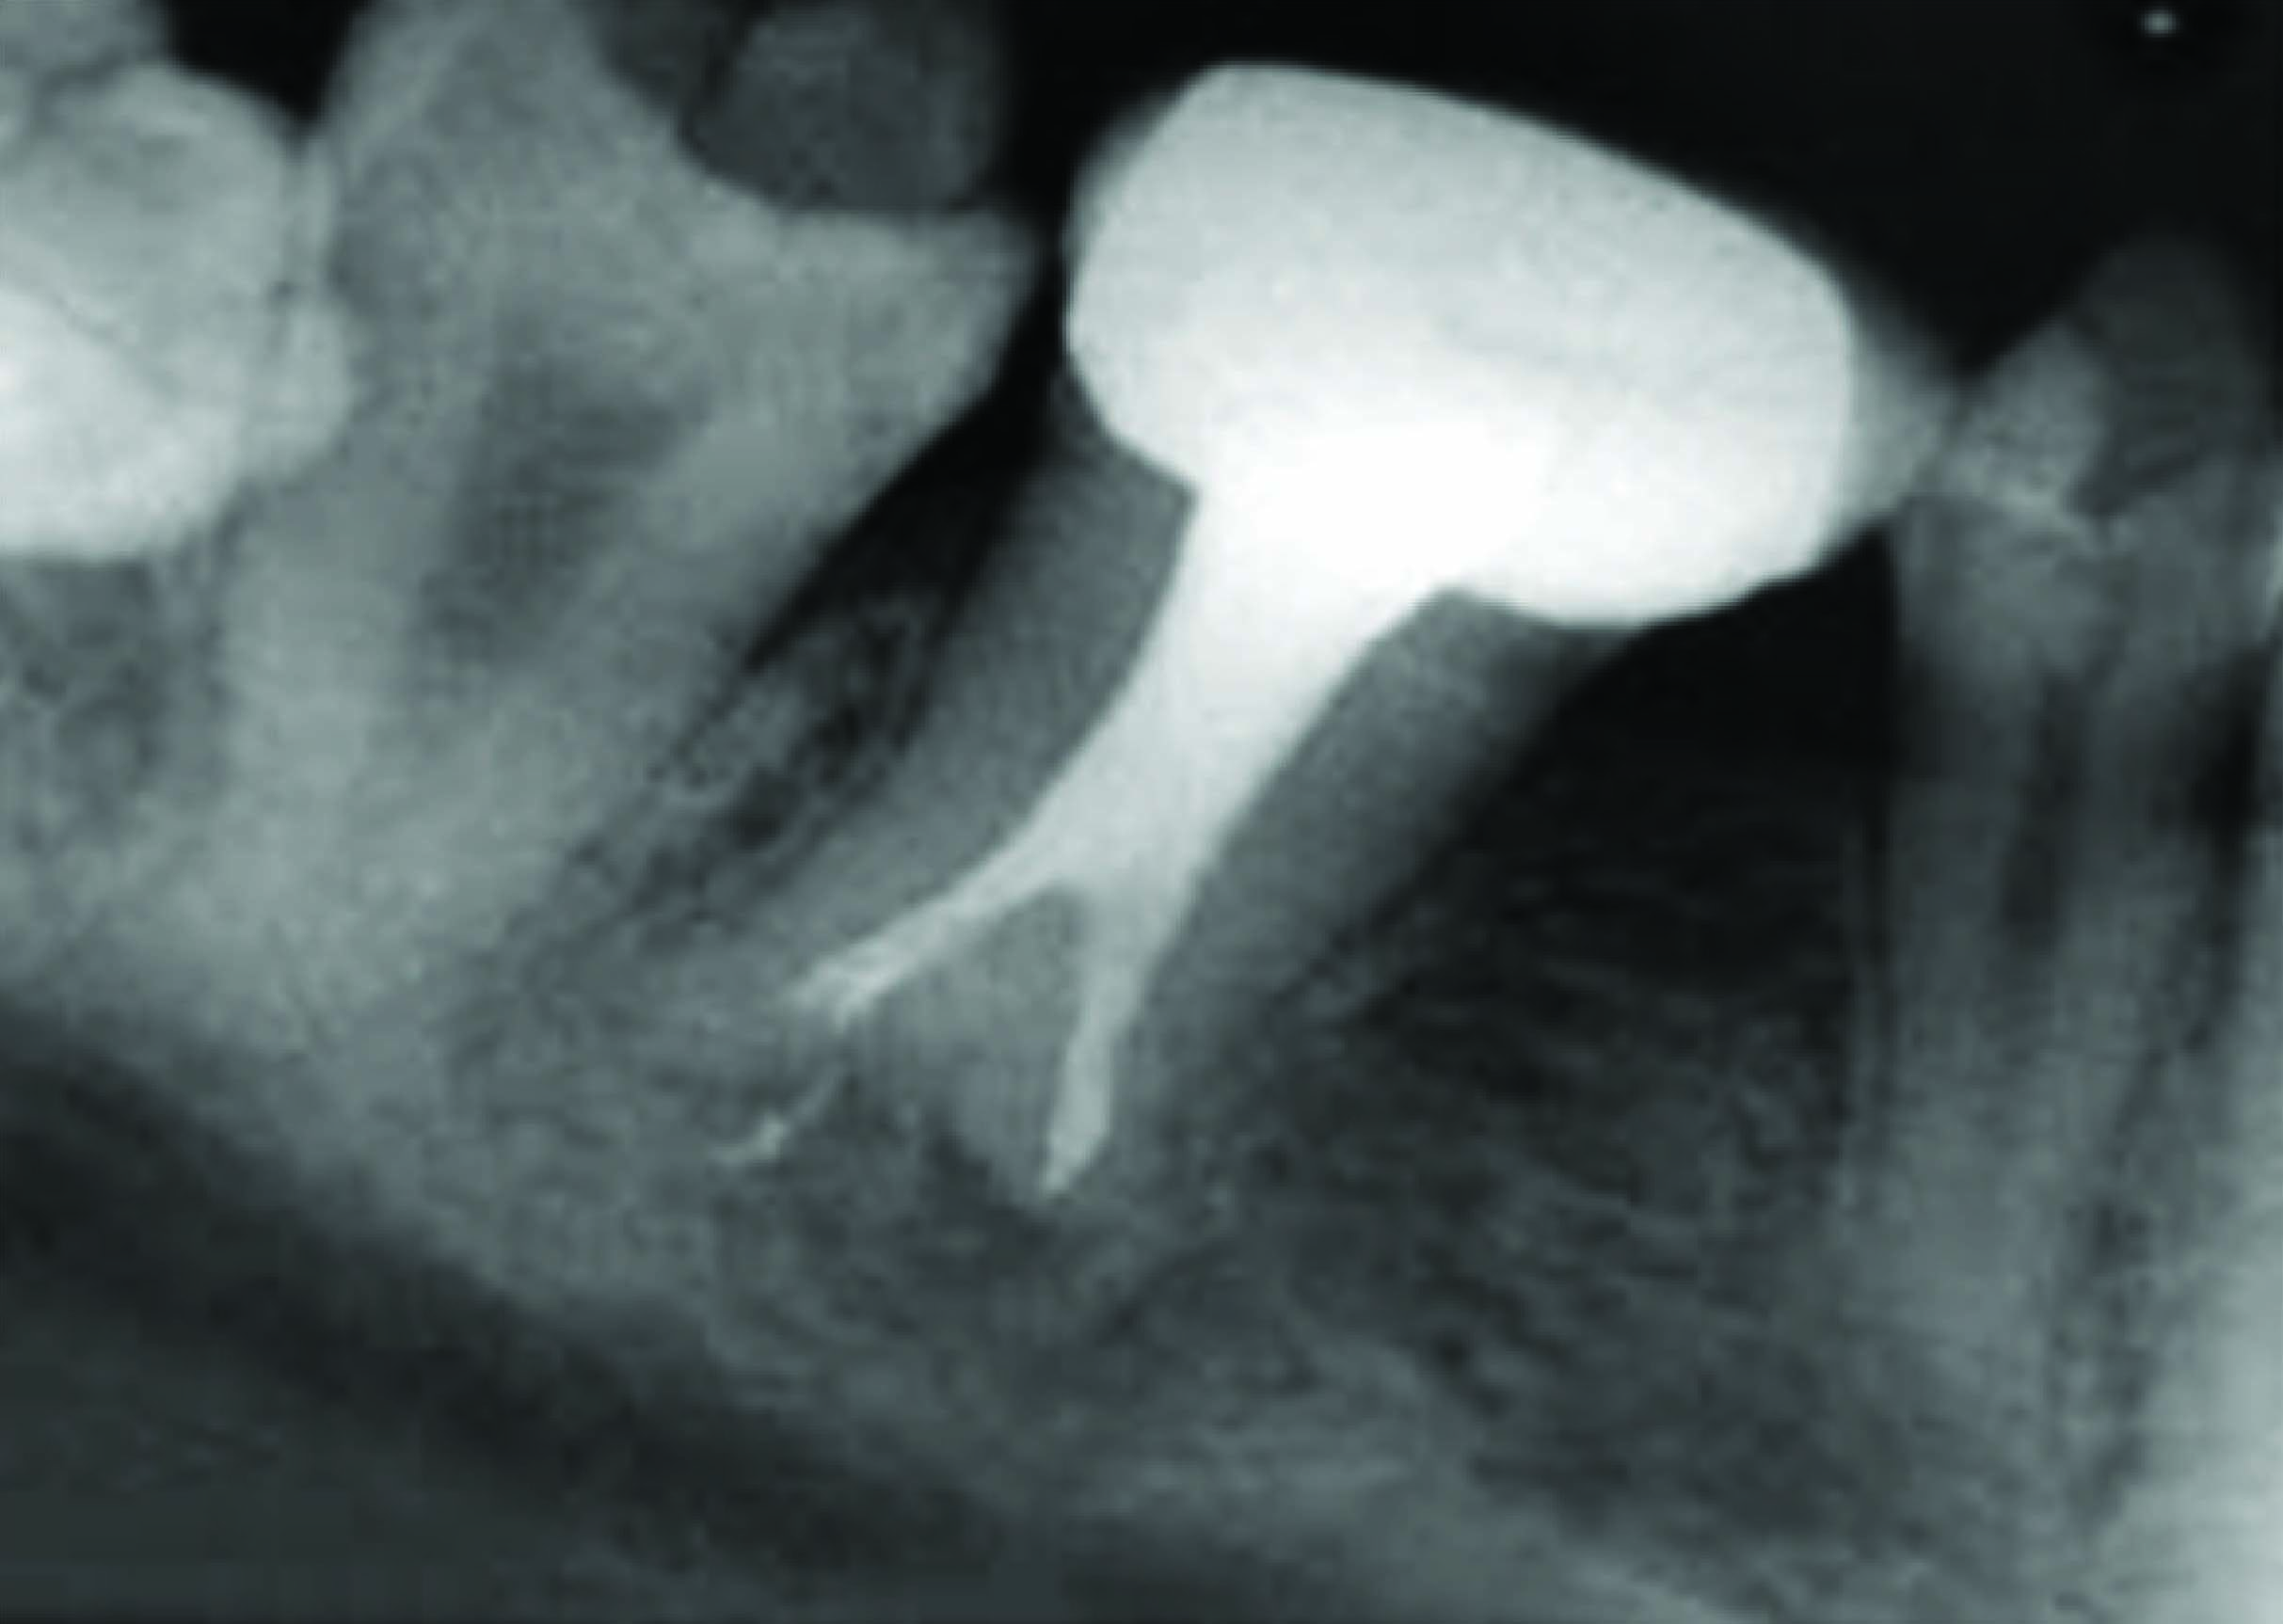

On clinical examination there was deep carious lesion in relation to 74 and 84 and grossly destroyed 64 and 85. Intraoral periapical radiograph of 74 and 84 revealed radiolucency involving pulp and enlarged pulp chamber with short roots suggestive of taurodontism [Table/Fig-1,2]. The teeth were subjected for clinical tests and diagnosis of chronic irreversible pulpitis was made in relation to 64, 74, 84, and 85. The teeth 74 and 84 were treated by multivisit pulpectomy procedure. Obturation was done with vitapex followed by semi permanent restoration with stainless steel crowns [Table/Fig-3].

Preoperative IOPA shows large pulp chamber suggesting taurodontism of 74

Preoperative IOPA shows large pulp chamber suggesting taurodontism of 84

Extraction followed by space maintainer was planned for 64 and 85 [Table/Fig-4, 5]. On further examination of the patient’s sibling’s similar characteristic radiographic finding of taurodontism was discovered. IOPA of 84, 85 region of brother [Table/Fig-6] and IOPA of 84 region [Table/Fig-7] of sister exhibited taurodontic characteristic. Suspecting this the mother was also subjected to radiographic procedure who to our great surprise exhibited taurodontic appearance of a previously endodontically treated 36 [Table/Fig-8].

IOPA shows endodontically treated 36 with large pulp chamber of the patient’s mother suggestive of taurodontism